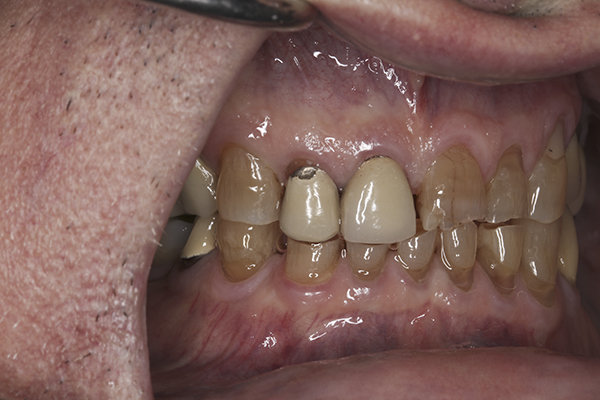

(7.) Preoperative anterior, open view. Note the significant amount of wear, erosion, and abfraction lesions.

Figure 7

(10.) Preoperative anterior, closed view. Note the end-to-end occlusion of the anterior teeth and the wear on the incisors and centrals resulting in no anterior or canine guidance.

Figure 10